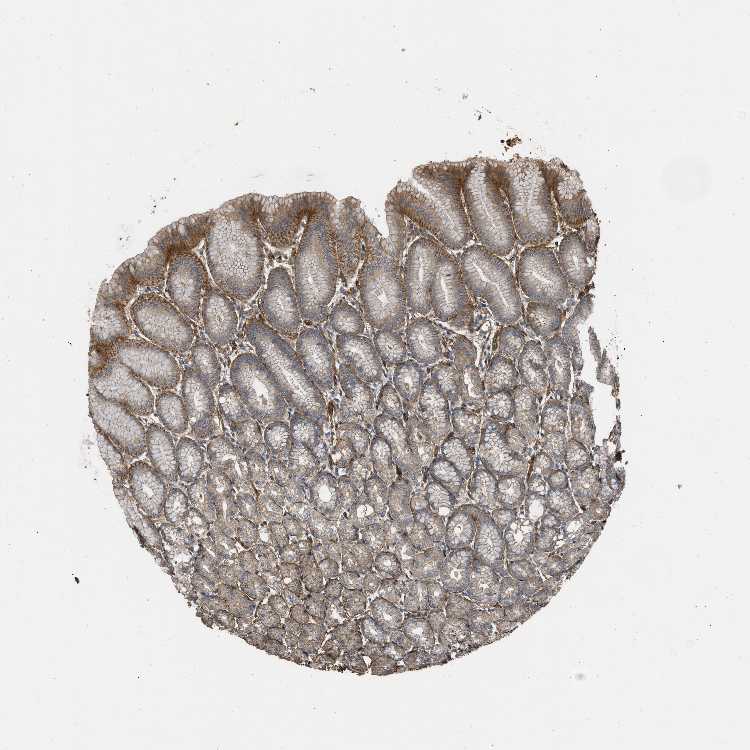

STOMACH 2 - Antibody stainingi

Antibody staining in the annotated cell types in the current human tissue is reported as not detected, low, medium, or high, based on conventional immunohistochemistry profiling in selected tissues. This score is based on the combination of the staining intensity and fraction of stained cells.

Each image is clickable and will lead to virtual microscopy that enables deeper exploration of all samples and also displays staining intensity scores, fraction scores and subcellular localization as well as patient and tissue information for each sample.

Antibody HPA018894Antibody CAB016348

Glandular cells MediumHigh